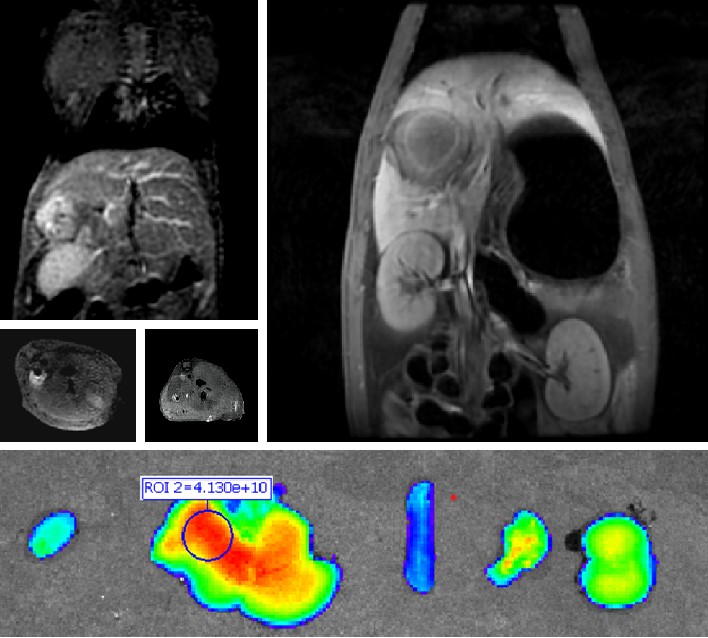

普利制药自主研发双模态造影剂PL002,首次提出通过整合磁共振技术,弥补现有荧光染料假阳性率高、透射深度有限等的短板,进而提升手术的精确性,降低手术过程中的风险,是全球首个获批临床试验的荧光/磁共振双模态造影剂,目前也已经获得美国FDA临床试验批件。